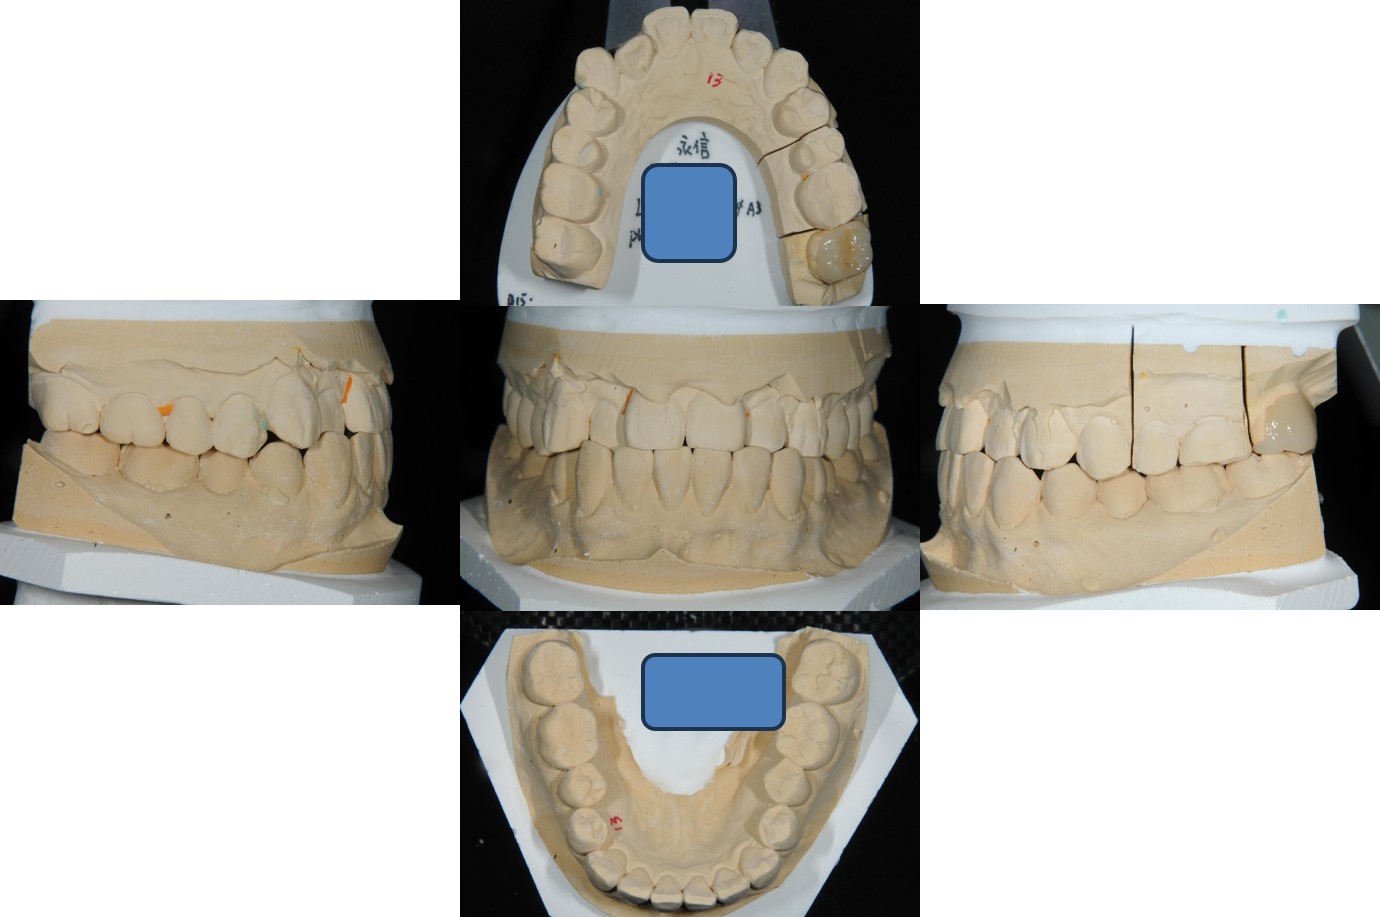

取面弓,上咬合器

陶瓷冠塊體製作